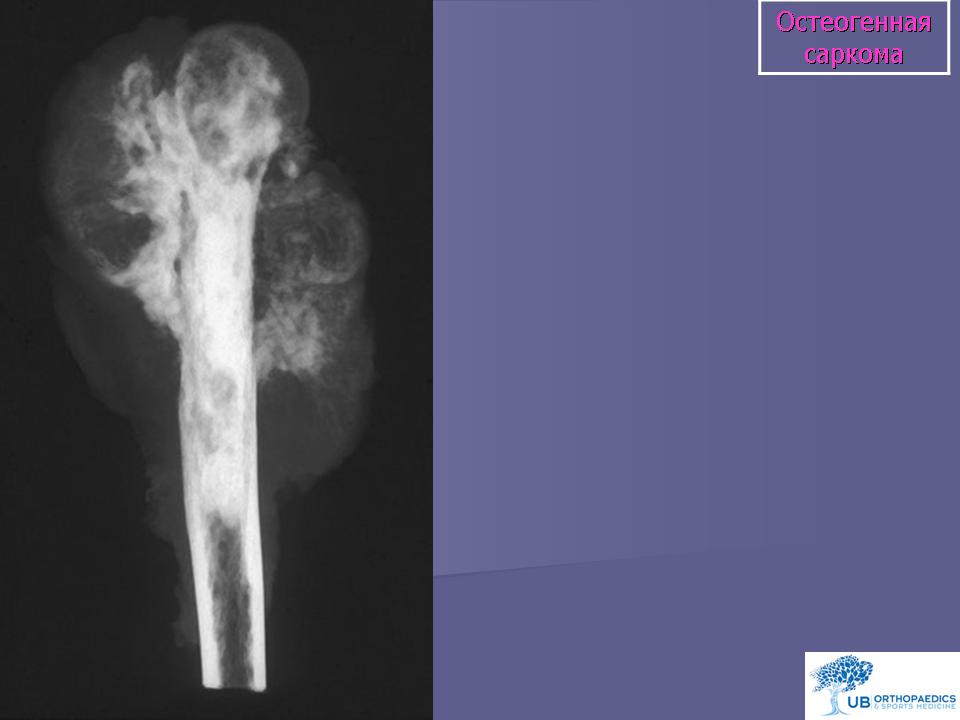

Остеосаркома (синонимы: центральная остеосаркома, остеофибросаркома, остеохондросаркома, медуллярная остеосаркома) - злокачественная опухоль, при которой новообразованная кость или остеоид продуцируются непосредственно самими опухолевыми клетками. Среди всех сарком кости, остеосаркома встречается наиболее часто и локализуется в длинных костях скелета.

Рентгенологическая картина. Типичной картиной является наличие очага смешанной деструкции кости с разрушением кортикальной пластинки и формированием мягкотканного компонента опухоли. В процессе роста опухоли, периост приподнимается или отслаивается от коркового слоя, это вызывает новое костеобразование, обычно проксимальнее основного узла, данное явление получило название козырька Кодмана. Зона поражения на рентгеновском снимке имеет различную плотность, а характер матрикса часто облаковидный. КТ и МРТ могут играть важную роль в определении распространенности опухолевого процесса. Радионуклидное сканирование скелета выявляет «skip» метастазы, многоузловые опухоли, системное поражение. В ряде клиник принято использовать артериографию, так как остеосаркомы - гиперваскуляризованные опухоли.